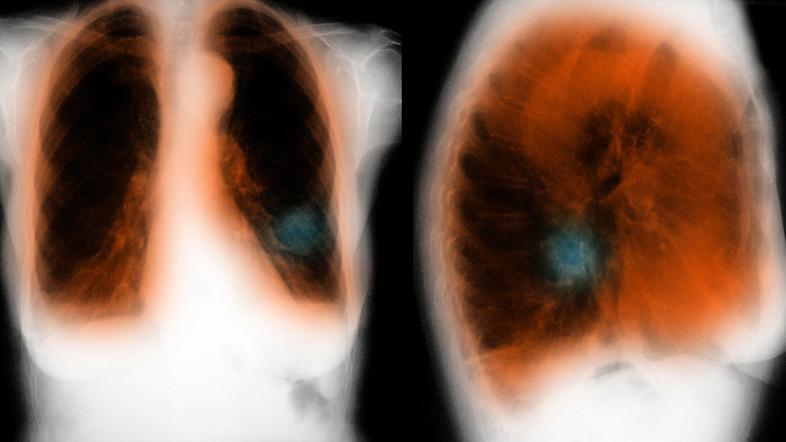

pljuča KOPB

Gre za kronično pljučno obolenje, pri katerem je normalen pretok zraka v pljuča zmanjšan, kar otežuje dihanje. Med ljudmi je znano tudi kot bolezen težke sape, pogosto tudi s pridruženim kašljanjem.